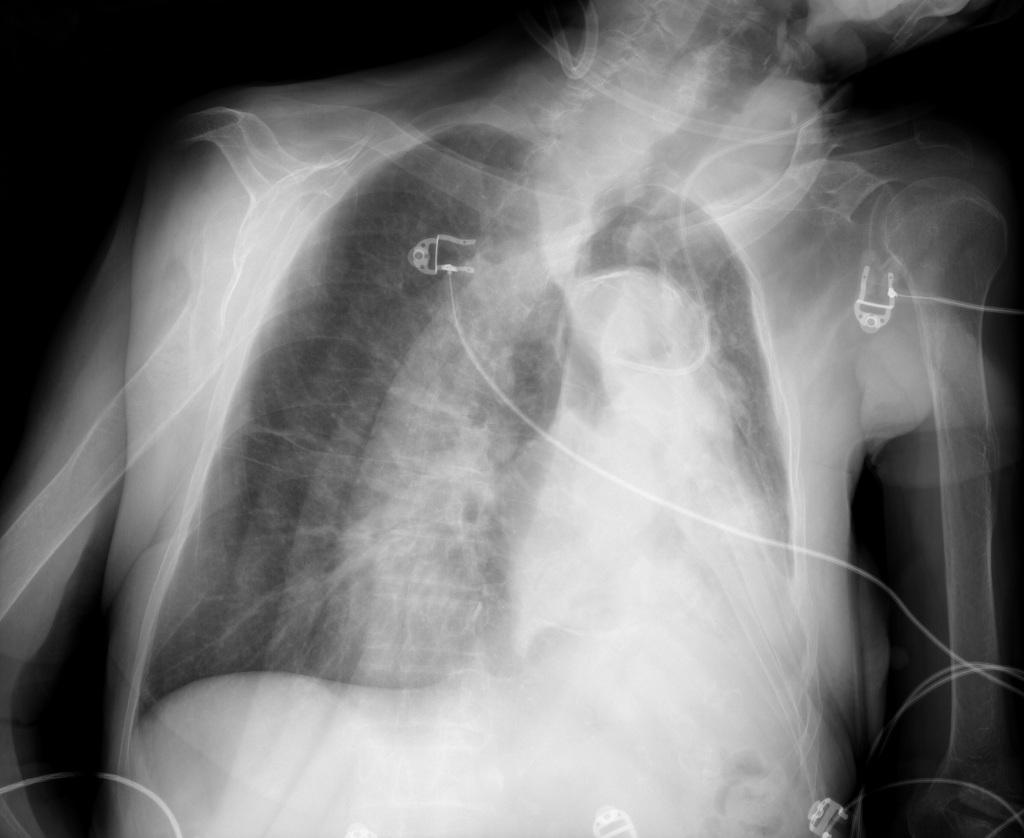

Lung image analysis

Chest X-rays is the most commonly acquired medical image worldwide. The advances of machine learning allow automated diagnosis of main lung pathologies, such as pneumonia and pneumothorax, with close-to-human performance. The automated diagnosis still however fails on patients with rare pathology manifestations, which precludes clinical integration of computerized solutions. The aim of this project is to develop solutions that will interact with physicians to improve lung disease diagnosis.